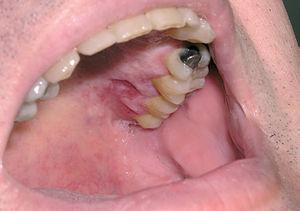

La afectación cutánea se produce en un tercio de los casos. Su aspecto clínico es similar al descrito en los pacientes con la enfermedad de Letterer-Siwe. Pueden observarse lesiones papulonodulares frecuentemente ulceradas en la mucosa oral o en la región vulvar (fig. 10) 12.

Fig. 10.--Lesiones ulceradas en la mucosa oral en un paciente con enfermedad de Hand-Schüller-Christian.